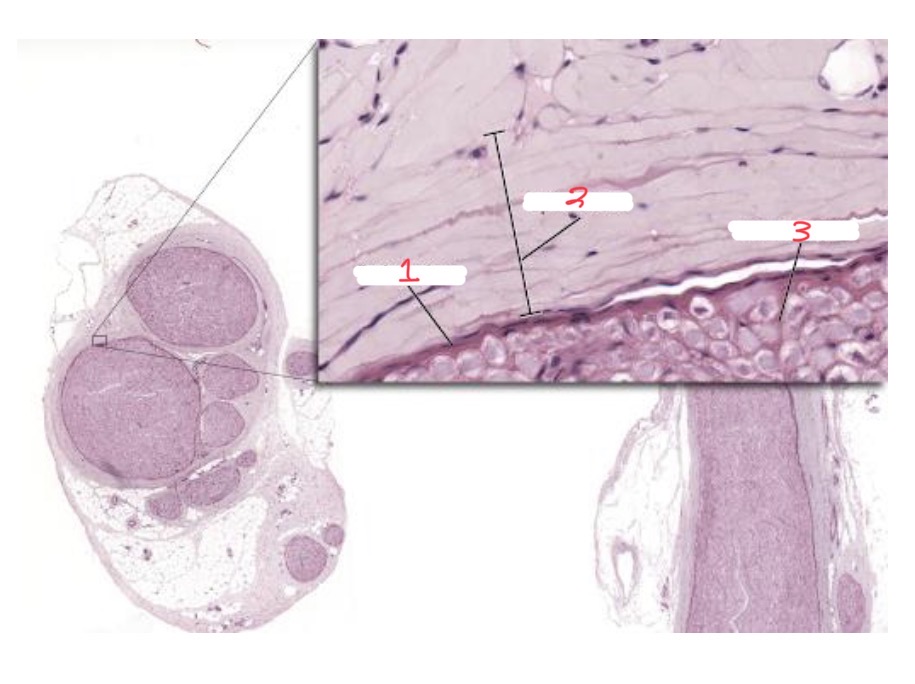

Peripheral nerve coverings

1

Perineurium

2

Epineurium

3

Endoneurium